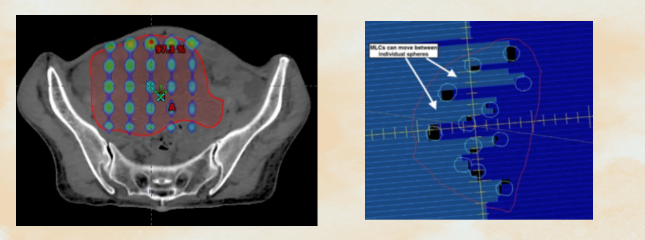

1. 2D GRID疗法:在二维中对肿瘤体积进行分割,通过带有规则间隔孔的网格准直器将照射野从宽光束变为笔形束,形成峰与谷间隔的剂量分布,将正常组织得到有效的保护。

2. 晶格放疗(Lattice Radiation Therapy, LRT):这是GRID疗法的3D进化版。我们在CT模拟定位后,基于患者的个体化肿瘤三维形貌,在治疗计划系统中虚拟设计一个三维的“剂量晶格”,将多个高剂量“球体”精确布设在肿瘤内部,特别是乏氧和增殖活跃的区域。这种“多点聚焦”式的设计,实现了治疗计划的高度个体化、精确化与安全化。

· 个体化计划设计:物理师与医师紧密合作,根据肿瘤的大小、形状、与周围危及器官的位置关系,个体化地确定晶格点的数量、位置和每个点处方剂量,并进行严格的剂量学验证。